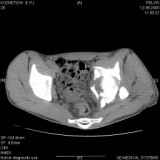

Уважаемые коллеги! Хотелось бы услышать совет по тактике лечения представлленого больного.

Поступил после лечения в одном изотделений области. Травма 2,5 месяца назад.

После выведения

из шока был произведен остеосинтез перелома бедра, предплечья, до перевода к нам проводилось

вытяжение по оси шейки бедра за стержень, введенный в большой вертел. На сегодня деформация

ригидна, клинически мобильности не определяется.